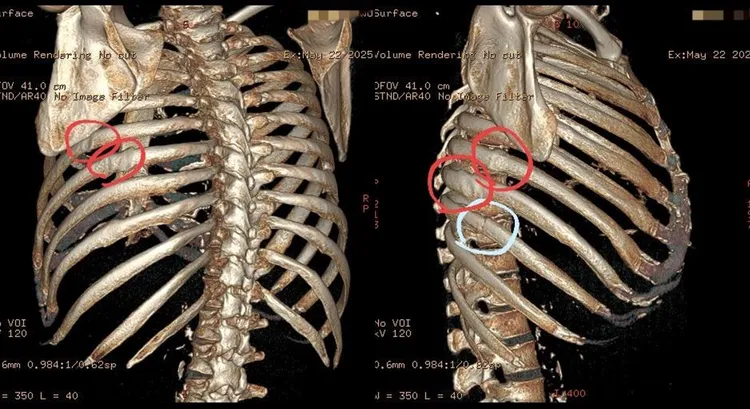

蘇一峰分享影像圖,紅圈是之前斷裂,白色是最近斷裂的肋骨。翻攝蘇一峰臉書

蘇一峰也分享影像圖表示,有四根肋骨是之前就斷裂,已經有癒合的舊傷,而有一根是最近斷裂尚未癒合的肋骨,詢問患者才知道,之前前咳嗽也有這樣的情形,原來已經因為咳嗽咳斷五根肋骨了。